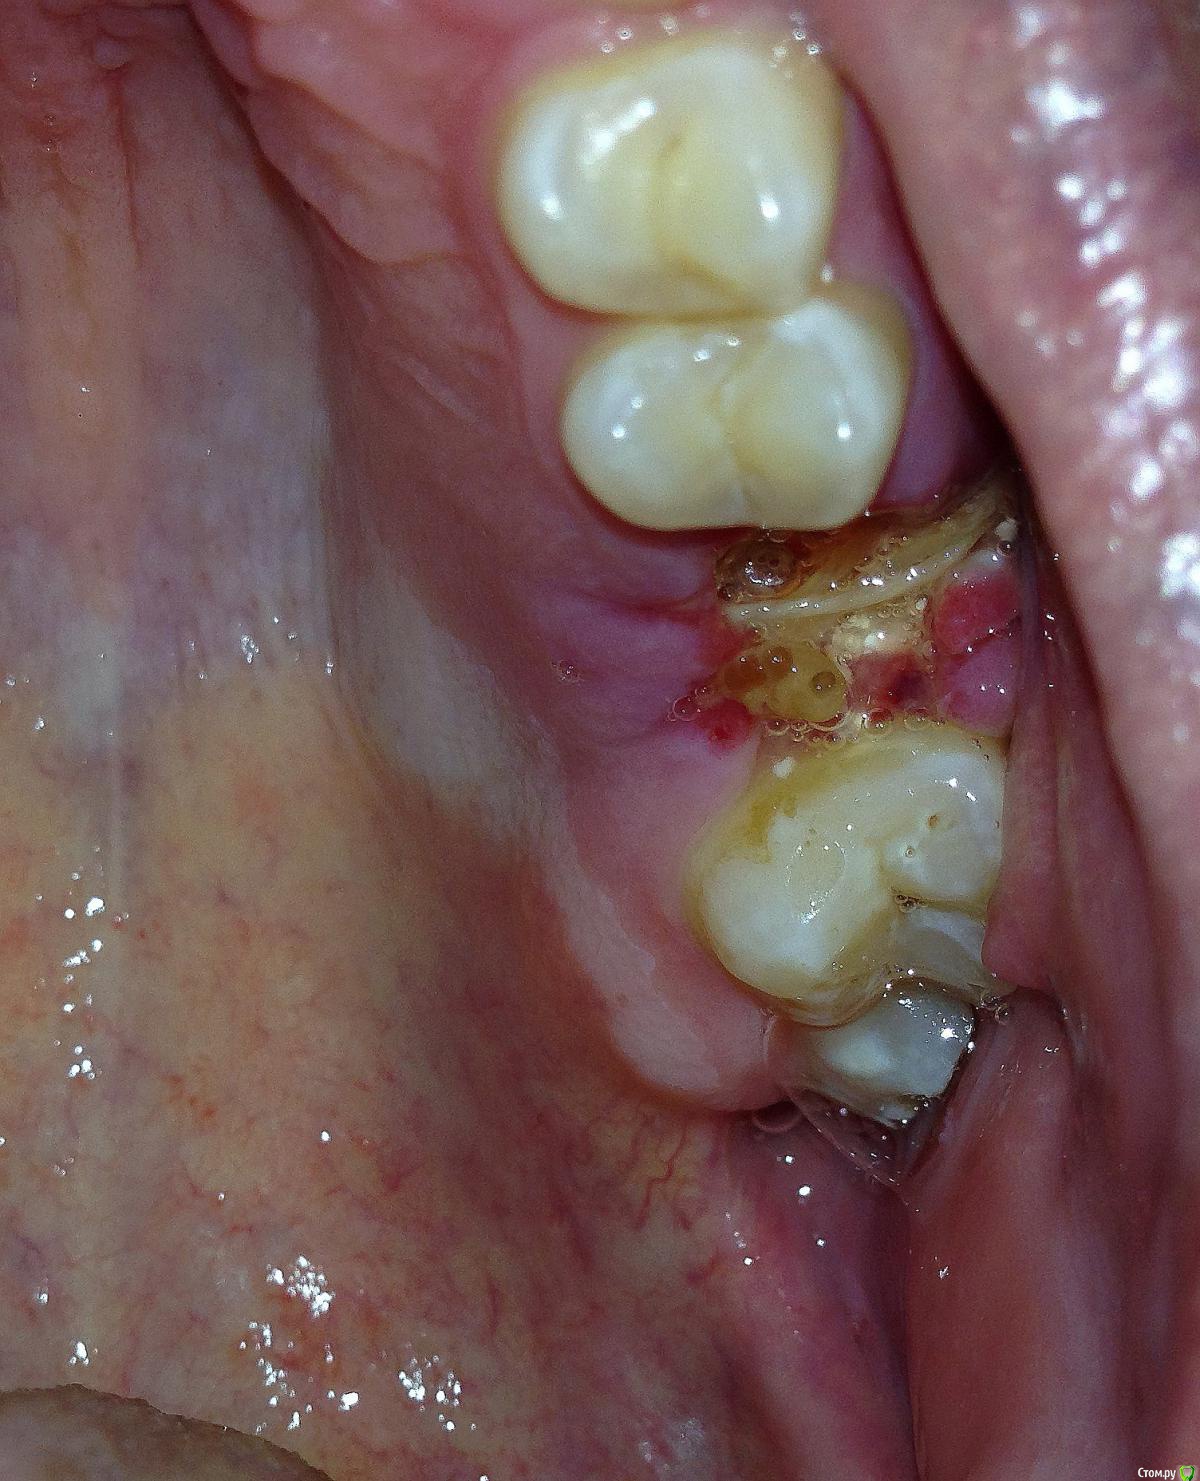

Евгений+ Опубликовано 1 октября, 2015 Поделиться Опубликовано 1 октября, 2015 (изменено) День добрый! 26 треснул под корень, подвижную стенку убрали.Зуб не беспокоит.Сделал КТ, при необходимости могу выложить полностью.Посоветуйте пожалуйста оптимальный план лечения с возможностью "жевать")) Изменено 1 октября, 2015 пользователем Евгений+ Ссылка на комментарий

major Опубликовано 1 октября, 2015 Поделиться Опубликовано 1 октября, 2015 КТ посмотрел.Удалять, с последующей имплантацией и протезированием. Слишком глубокий скол. Ссылка на комментарий

колесников Опубликовано 1 октября, 2015 Поделиться Опубликовано 1 октября, 2015 У вас там на 3ёх корнях по кистогранулёме и полип в пазухе. Дно пазухи перфорировано ,корни и что неприятно,корневой наполнитель контактируют с полипом. Сохранять нельзя-удалять. Обратитесь к отоларингологу,эндоскопически желательно исследовать полип. Если просто пролиферация интимы-можно удалять и ставить имплант одномоментно,если это грибковый полип-вначале удаляете зуб и полип ,а только затем решаете вопрос с пластикой. Ссылка на комментарий